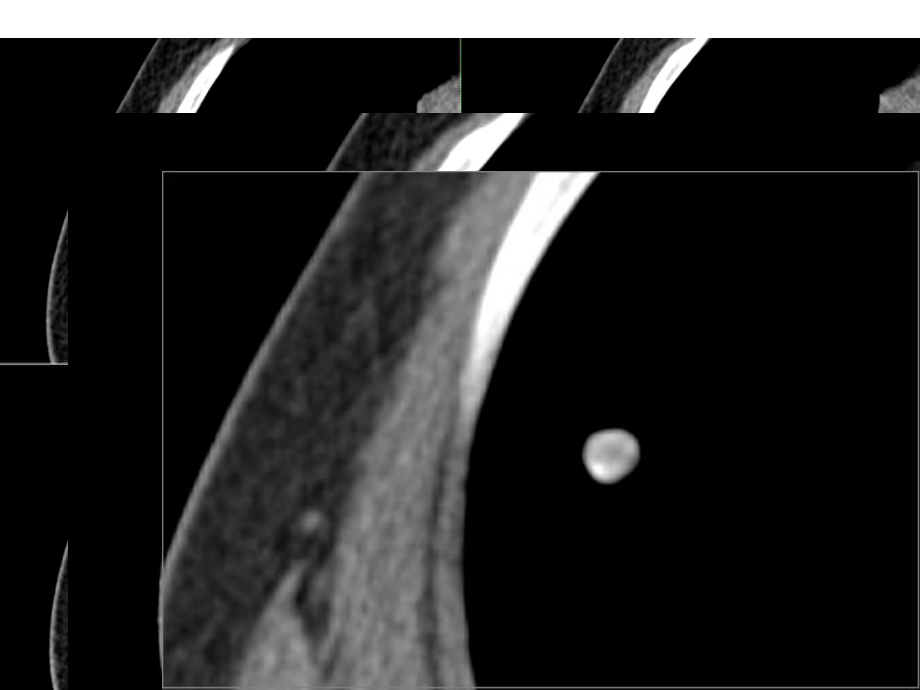

1、病例病例1:男性,:男性,47岁岁界限清晰的高密度与低密度之分病例病例2:女性,:女性,35岁岁界限清晰的高密度与低密度之分病例病例3:女性,:女性,50岁岁薄层薄层CT纵隔窗为纵隔窗为3.75mm薄层薄层CT(肺窗为(肺窗为2.5mm薄层薄层CT纵隔窗为纵隔窗为3.75mm病例病例4:女性,女性,53岁岁 女性,女性,44岁岁病例病例病例病例病例病例男性,男性,68岁岁女性,女性,50岁岁病例病例病例病例肺硬化性血管瘤肺硬化性血管瘤pulmonary sclerosing hemangiomsclerosing hemangiom of the lung(PSH/SHL)定义及病因定义及病因

5、所见较难与支气管肺癌相鉴别影像学影像学CT 类圆形孤立性肺结节(类圆形孤立性肺结节(SPN)或肿块)或肿块 轮廓清楚、边缘光滑、锐利轮廓清楚、边缘光滑、锐利 可有浅分叶和小钙化可有浅分叶和小钙化 多数位于肺边缘近胸膜下多数位于肺边缘近胸膜下 CT平扫:界限清晰的高密度与低密度之平扫:界限清晰的高密度与低密度之分;密度均匀,偶见分;密度均匀,偶见空气新月征空气新月征(特征性(特征性表现)。表现)。空气新月征象病理空气新月征象病理 病灶周围有纤维假性包膜形成,瘤组织因病灶周围有纤维假性包膜形成,瘤组织因毛细血管增生延长,管壁玻璃样变,并形毛细血管增生延长,管壁玻璃样变,并形成乳突样突起深入气道,使

6、气道变成不规成乳突样突起深入气道,使气道变成不规则的裂隙,从而使肿瘤与包膜间形成半环则的裂隙,从而使肿瘤与包膜间形成半环状游离空气腔隙状游离空气腔隙 未分化的肺间质细胞不断增生和透明样变,未分化的肺间质细胞不断增生和透明样变,围绕支气管导致远端的空气腔隙扩大围绕支气管导致远端的空气腔隙扩大影像学影像学CT增强:增强:1. 低密度区基本不强化,高密度区强化低密度区基本不强化,高密度区强化明显明显2. 肿块强化明显且出现混杂密度肿块强化明显且出现混杂密度3. 逐渐均匀强化逐渐均匀强化4. 贴边血管征:即位于肺门旁的病灶周贴边血管征:即位于肺门旁的病灶周围见血管呈绕球状强化围见血管呈绕球状强化5.